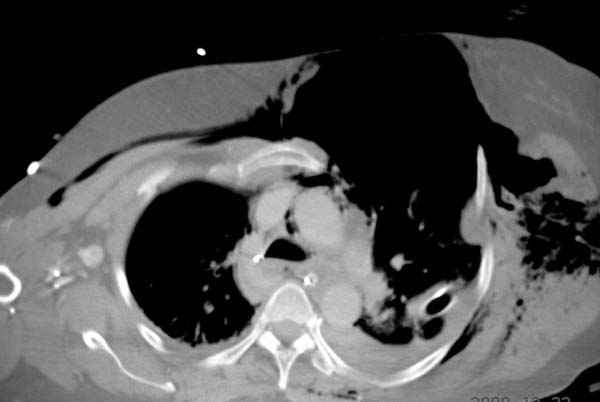

К нам поступила больная 56 лет после автоаварии в бессознательном состоянии, которая срочно заинтубирована в приемном отделении и сделаны необходимые исследования. Данные КТ и рентген показали перелом дистального бедра и Dissociation upper extremity - закрытый отрыв левой верхней конечности на уровне грудинно-ключичного сочленения и множественные переломы ребер.

На поверхности грудной клетки из-за полного разрыва грудной мышцы под кожей заметно биение сердца и след от ремня безопасности. Грудная клетка расширена из-за смещения верхней конечности вверх и латерально. Признаков васкулярного повреждения нет, и из-за отсутствия сознания не смогли определить наличия повреждения нервов.

На седьмые сутки нами совместно с торакальным хирургом сделана операция по фиксации грудинно-ключичного сочленения и переломов ребер.

После кожного разреза обнаружили полный разрыв грудной мышцы и повреждение перикард от уровня второго до восьмого ребер. Хирург находился с нами и после нашей работы зафиксировал повреждение перикарда и разрыв грудной мышцы.